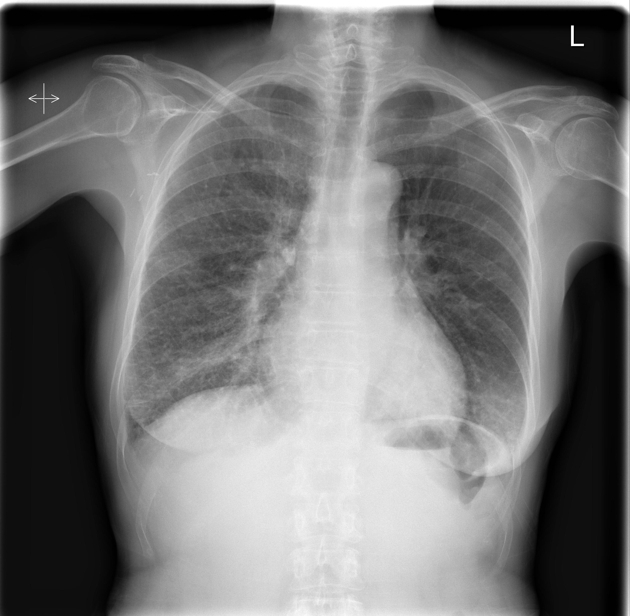

CXR: Interstial Lung Disease DDx

Lymphangitic Carcinomatosis:

Usually arises from adenocarcinomas such as:

Findings:

DDx: (these are also for interlobar septal thickening)